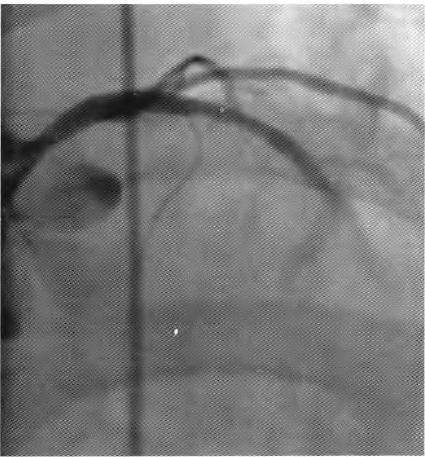

患者择期于10月25日行冠状动脉介入治疗,术前常规给予地塞米松10 mg静脉注射,右侧桡动脉穿刺成功后,经鞘管送多功能造影导管至主动脉窦部,对比剂选择碘帕醇(商品名:碘必乐),导管“吾烟”后数秒钟,患者血压骤然降低至50/30 mmHg,心率逐步增快至90次/min左右,予羟乙基淀粉130/0.4氯化钠注射液(万汶)加压快速静脉滴注100 mL,反复3次静脉注射多巴胺3 mg,血压65/40 mmHg左右,约3 min后心率降至40次/min左右,监护示室性逸搏心律,继之心跳、呼吸骤停。持续胸外按压,气管插管机械通气,持续静脉泵入肾上腺素0.2仙g/(kg•min),并间断4次静脉注射肾上腺素0.5 mg,血压维持在105/50 mmHg左右,进一步行左室造影,见图1。以及左冠状动脉造影,见图2。氧饱和度降至75%,考虑对比剂致高敏反应,引起过敏性休克,静脉滴注甲泼尼龙500mg,经右侧股动脉路径行主动脉内球囊反搏术(intra.aortic balloon pump,IABP)治疗,同时联系外科、麻醉科、体外循环科经左侧股动脉一股静脉行体外膜肺氧合(extra—corporeal membrane oxygenation,EC—MO)支持治疗。ECMO置人后将患者由导管室转送至冠心病监护病房(coronary care unit,CCU)继续抢救治疗,床边心脏超声,见图3。提示室间隔水肿(厚度1.53 cm)。在置人ECMO初期维持绝对镇静,下调直至停用血管活*药性**物,心律以室性逸搏心律为主(持续约48 h),偶然有室速、室颤发作,未作处理。在置人ECMO第3天因急性肾衰竭行床旁连续静脉静脉血液滤过(continuous veno—venous hemofiltration,CVVH)治疗,第4天后患者心率、血压稳定,复查心脏超声提示左心室射血分数40%,撤除ECMO,此后依次拔除气管插管、撤除IABP以及停止CVVH等治疗,患者恢复良好,于11月14日出院。

图2左冠状动脉造影未见冠脉损伤或冠脉急性血栓事件.冠状动脉前向血流瘀滞

在冠状动脉介入诊疗术中发生心脏骤停,对于尚处于心肌梗死(尤其是急性ST段抬高型心肌梗死)急性期的病例,要首先考虑心肌梗死后机械并发症(如心室游离壁破裂、室间隔穿孔等)、冠脉急性血栓栓塞事件以及医源性冠脉损伤等,并迅速行相关检查措施排查,如能排除以上危重情况,则要考虑对比剂导致过敏性休克。该患者术中左室造影排除心室游离壁破裂,左冠状动脉造影排除左主干或左冠血管急性血栓栓塞事件以及医源性冠脉损伤,再结合患者存在药物(多种抗生素)过敏史,因此,诊断对比剂致过敏性休克明确。后期心脏超声提示“心肌水肿”,亦是器官组织对过敏的一种表现。